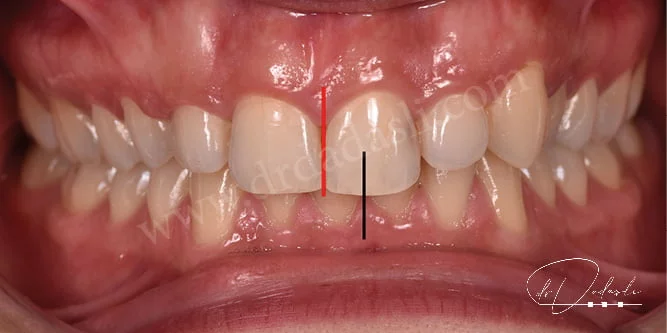

- Dişlerin orta hatlarının kayması (Şekil 7) – üst iki orta keser dişin ortası ile alt iki orta keser dişin ortasının çakışmamasıdır.